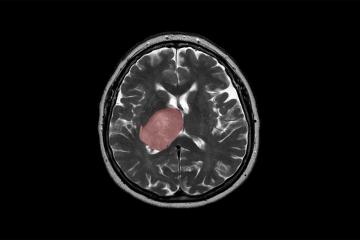

Stories from the University of Toronto community Geochemist draws on billion-year-old water discovery to aid green energy transition Latest news January 12, 2021 U of T, international researchers develop more efficient two-sided solar cells January 11, 2021 Social media's decision to dump Trump too little, too late: U of T's Megan Boler January 11, 2021 How a researcher at U of T's Citizen Lab helped ID Capitol Hill rioters: Toronto Star January 11, 2021 Thing theory: U of T course explores how objects shape people January 8, 2021 AMD’s supercomputing partnerships with U of T, other universities to take centre stage at CES January 8, 2021 Over-policing in Black communities to be explored in new U of T public health course January 8, 2021 Urban studies course forges bond between students and seniors during COVID-19 January 7, 2021 ‘They shall not be forgotten’: U of T marks first anniversary of Flight 752 tragedy January 7, 2021 'I feel hope': A devastating diagnosis prompted U of T alumna Natalie Jenner to pick up the pen January 7, 2021 U of T Scarborough's new director of campus safety brings a focus on equity, diversity and inclusion January 6, 2021 U of T expert calls Capitol Hill violence an ‘extremely disturbing challenge to American democracy’ January 6, 2021 Drought, deforestation in Amazon exacerbate COVID-19 impact: U of T researcher January 6, 2021 Ellie Hisama named dean of U of T’s Faculty of Music January 5, 2021 'The next big step': U of T researchers pursue a treatment for vision loss January 5, 2021 U of T Engineering launches 3D-printing course to prepare students for booming field January 5, 2021 Ice arches holding Arctic's ‘Last Ice Area’ in place are at risk, U of T researcher says January 4, 2021 Brain cancer linked to tissue healing: U of T researchers January 4, 2021 U of T researchers develop environmentally friendly surgical mask for front-line workers January 4, 2021 A perfect fit: U of T startup collaborates with researchers to launch shoe-sizing app December 30, 2020 Faculty, alumni and supporters named to Order of Canada December 22, 2020 The year in pictures: U of T News looks back at 2020 Pagination First First page Prev Previous page 122 123 124 125 126 Next Next page Last Last page